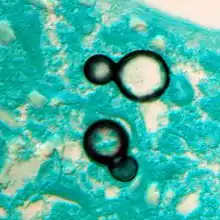

Granuloma with early suppuration. Fungal organisms difficult to recognize at this low magnification.

Large yeast-like fungi seen within giant cells at arrows.

Large yeast-like fungi seen within giant cells at arrows. Budding yeasts in cytoplasm of giant cells at arrows. Broad-based budding and double contoured cell wall seen in the giant cell in the center is characteristic of Blastomyces dermatitidis.